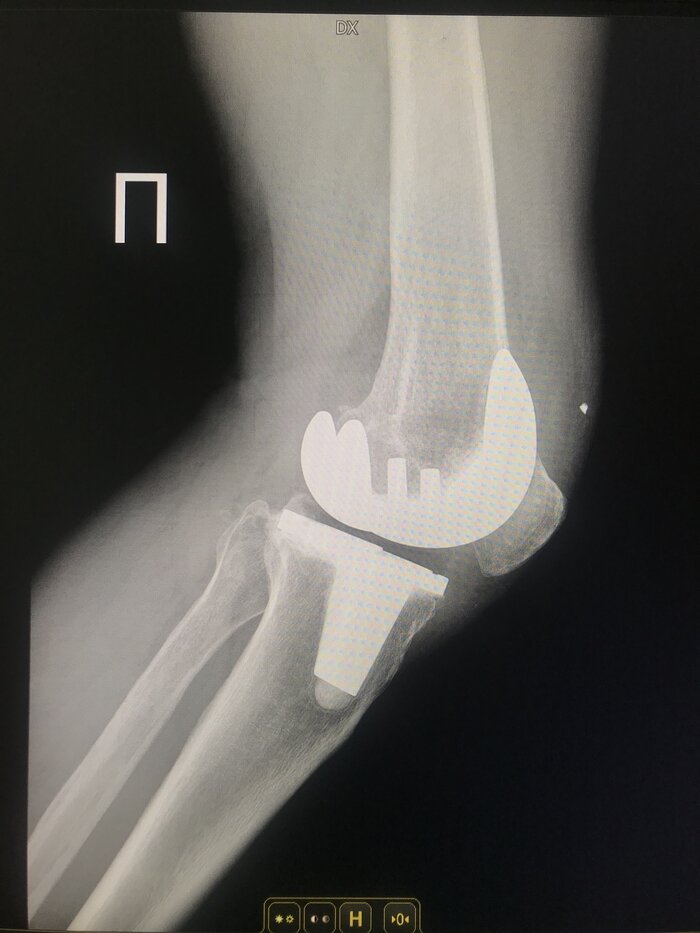

Продукт спорта, человек занимался шорт-треком всю жизнь.

Это он же!)) возраст 70 лет, мужчина.